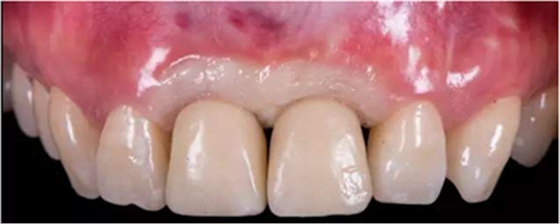

治療效果

修復(fù)前

修復(fù)后

本病例中通過(guò)對(duì)患者修復(fù)體佩戴后的舌側(cè)、頰側(cè)、左側(cè)、右側(cè)以及微笑照的采集,充分展示修復(fù)體在口內(nèi)的佩戴情況,可以看到無(wú)論顏色還是與鄰牙的匹配適宜度都是非常高,也比較吻合年輕女性對(duì)美觀的要求。同時(shí),通過(guò)術(shù)后多次隨訪及跟蹤患者后期使用狀況,患者也對(duì)修復(fù)效果十分滿意。